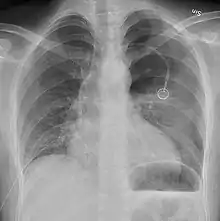

Chest X-ray showing the features of pneumothorax on the left side of the person (right in image)

A plain chest radiograph, ideally with the X-ray beams being projected from the back (posteroanterior, or "PA"), and during maximal inspiration (holding one's breath), is the most appropriate first investigation.[25] It is not believed that routinely taking images during expiration would confer any benefit.[26] Still, they may be useful in the detection of a pneumothorax when clinical suspicion is high but yet an inspiratory radiograph appears normal.[27] Also, if the PA X-ray does not show a pneumothorax but there is a strong suspicion of one, lateral X-rays (with beams projecting from the side) may be performed, but this is not routine practice.[14][18]

It is not unusual for the mediastinum (the structure between the lungs that contains the heart, great blood vessels and large airways) to be shifted away from the affected lung due to the pressure differences. This is not equivalent to a tension pneumothorax, which is determined mainly by the constellation of symptoms, hypoxia, and shock.[13]

The size of the pneumothorax (i.e. the volume of air in the pleural space) can be determined with reasonable accuracy by measuring the distance between the chest wall and the lung. This is relevant to treatment, as smaller pneumothoraces may be managed differently. An air rim of 2 cm means that the pneumothorax occupies about 50% of the hemithorax.[14] British professional guidelines have traditionally stated that the measurement should be performed at the level of the hilum (where blood vessels and airways enter the lung) with 2 cm as the cutoff,[14] while American guidelines state that the measurement should be done at the apex (top) of the lung with 3 cm differentiating between a "small" and a "large" pneumothorax.[28] The latter method may overestimate the size of a pneumothorax if it is located mainly at the apex, which is a common occurrence.[14] The various methods correlate poorly, but are the best easily available ways of estimating pneumothorax size.[14][18] CT scanning (see below) can provide a more accurate determination of the size of the pneumothorax, but its routine use in this setting is not recommended.[28]